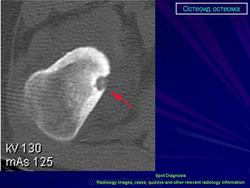

Мужчина, 18 лет, с жалобами на боли в пальце, особенно в ночное время. Произведена рентгенография и КТ.

Рентгенограмма и КТ-изображение типичной остеоид остеомы в проксимальном отделе большеберцовой кости.

КТ изображение фиксирует периостальную реакцию, утолщение кортикльного слоя, очаг (стрелка) с центральной минерализацией. Имеет место реактивный склероз костного мозга (*), прилегающего к очагу.

Аксиальная КТ фиксирует очаг (стрелка), окруженный реактивным надкостничным образованием костной ткани.